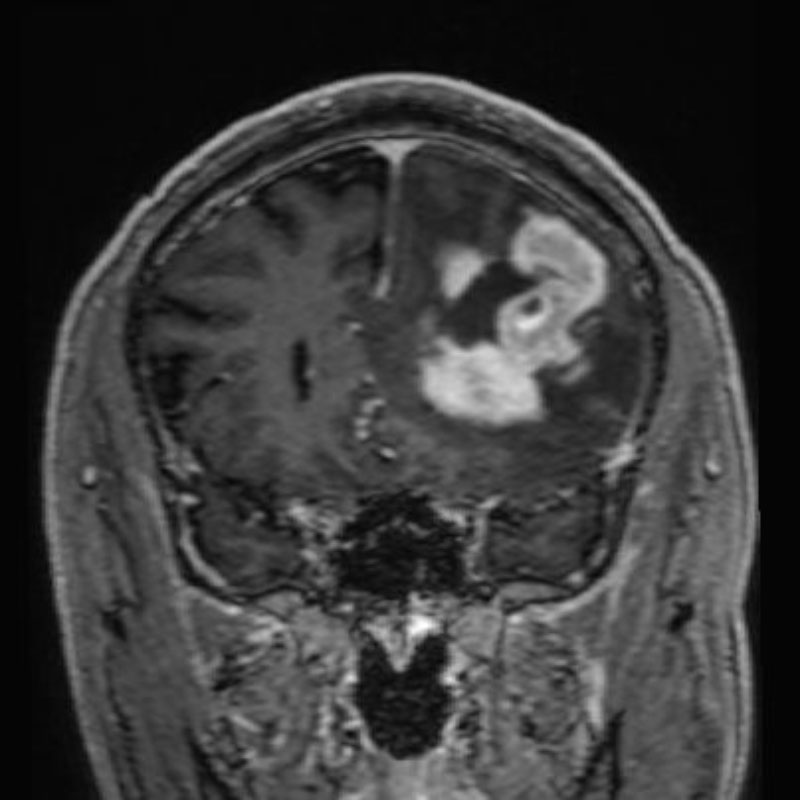

断層撮影

手術前1

手術前2